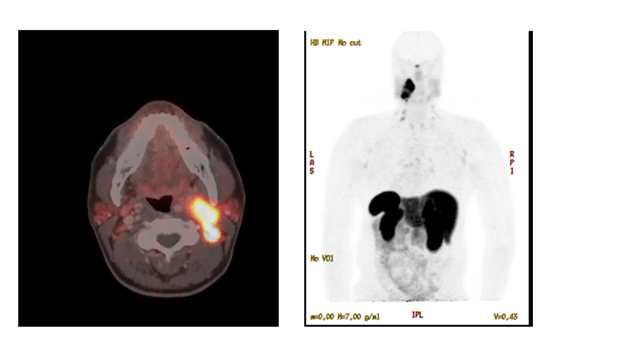

The patient underwent biochemical testing, which showed elevated serum normetanephrines of 252 pg/mL and elevated serum metanephrines of 155 pg/mL, both done by LC/MS/MS. 24-hour urinary fractionated normetanephrines and metanephrines were also elevated to three times the upper limit of normal. A 24-hour urine dopamine level was normal. Patient then underwent a dotatate PET/CT scan, which redemonstrated the same cervical carotid sheath mass with associated lymphadenopathy — all of which were strongly dotatate positive/avid (see image 2). After this, the patient was started on alpha blockade with doxazosin, which was titrated to 2 mg daily. He then underwent fine needle aspiration (FNA) of the largest left IIb lymph node. Resulting cytology revealed a less than optimal specimen with suspicion for neoplasm. Chromogranin A immunostaining of the biospecimen was increased, consistent with a diagnosis of paraganglioma. Thyroseq v3 did not identify other genetic mutations. After the above evaluation, the patient was referred to head and neck surgery and radiation oncology. The patient was presented at their tumor board, and ultimately, it was decided the mass would be difficult to resect given its location and size. The decision was made to proceed with radiation therapy. The patient was also referred to the genetics clinic with genetic testing still in process at this time.

Image 2. Dotatate PET/CT scan of head and neck showing the head and neck paraganglioma.